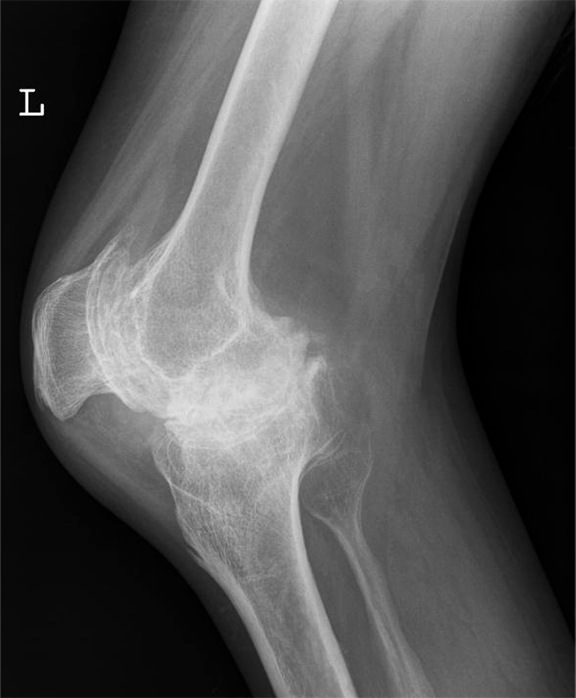

A 34-year-old male with hemophilia A presented to the emergency department with pain and swelling in his left knee following a minor fall. He was known to suffer from advanced arthropathy and was awaiting a total knee replacement. On clinical examination, the left knee was swollen and tender with a reduced range of movement. Plain radiograph (antero-posterior and lateral views) performed (Figure 1) (Figure 2)excluded a fracture or dislocation but demonstrated classic appearances of hemophilic arthropathy with severe secondary degenerative changes. He was discharged with adequate simple analgesia and outpatient follow-up appointments with his hematologist and physiotherapist.

Figure 2: Lateral radiograph of the knee showing squared inferior margin of the patella and severe degenerative changes in the patellofemoral and tibiofemoral compartments.

Hemophilia is an inherited, X-linked recessive disorder caused by deficiency of plasma clotting factors VIII, IX or XI. It manifests in males while females are asymptomatic carriers. Hemophilic arthropathy results from repeated episodes of hemarthrosis, blood within the joint damages the articular cartilage directly. [1] Large joints (knee, ankle, elbow, and shoulder) are usually affected. The classic appearance of hemophilic arthropathy in the knee is shown in Figures 1 and 2, i.e., widened intercondylar notch, bulbous femoral condyles, flattened condylar surfaces and squared inferior margin of the patella. [2] Due to repeated episodes of hemarthrosis, our patient also had severe secondary osteoarthritic changes with near-total joint space loss. Hemophilic arthropathy most often begins in the first or second decade of life and bleeding episodes tend to recur in the same joint with gradual progression to joint destruction. Recurrent hemarthrosis inevitably leads to synovial hyperplasia, subchondral resorption, erosions, articular cartilage destruction, joint space narrowing, and osseous proliferation. Periarticular osteoporosis and epiphyseal overgrowth occurs due to associated joint hyperemia. Clinical presentation varies according to disease severity with pain and joint swelling during acute episodes of hemarthrosis and progressive loss of joint function in longstanding cases. Prophylactic replacement of deficient clotting factors in the first or second decade of life may prevent or delay joint destruction in children with severe hemophilia. [3] Patients who present with an acute bleeding episode require adequate pain relief, prompt administration of deficient clotting factor and rest. Patients who suffer from repeated hemarthrosis despite optimal conservative management may benefit from synovectomy. Patients with end stage disease may require surgical arthrodesis or total joint replacement to control pain and restore some function as planned for our patient.